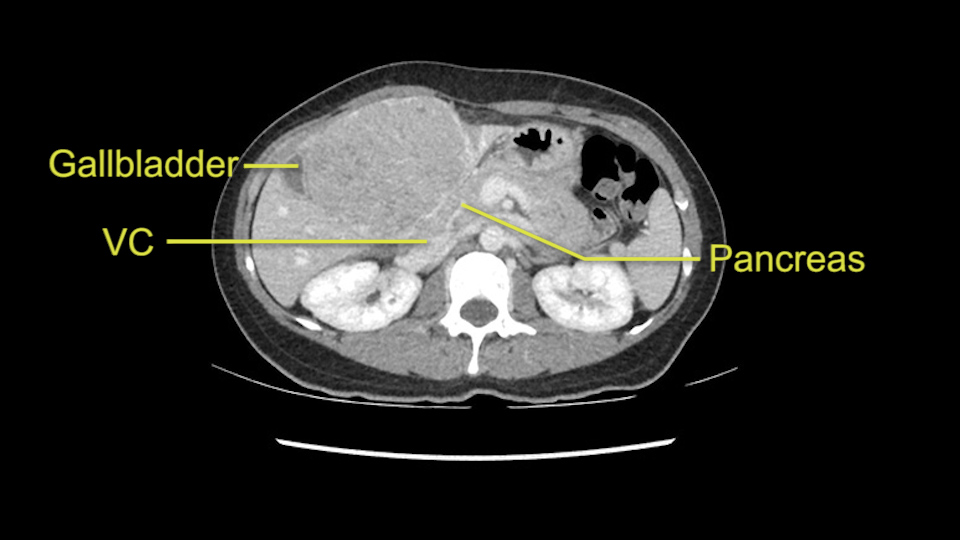

So the issue with regards to resection. A left sided tumor. I believe I can see the falciform ligament right here so we’re looking at a resection of Segments 2, 3 of the left lobe of the liver. The left portal vein is right there. I think we’ll be wiser to take the left portal vein and therefore get well into Segment 4 and do a left hemihepatectomy. Certainly, one does not need to take the middle hepatic vein; it’s miles from the tumor.

We note that the tumor is pushing on the gallbladder but I think that’s probably external for the most part. I think that’s extrahepatic. I believe that Segment 4b is probably free of tumor. I’d have to say that it's tempting, particularly looking at the coronals, to consider a very limited resection. Where you’d just chip it off the bottom of Segment 3 and do a limited Segment 3 resection. I’d be concerned about the oncologic margins. I believe that the best oncologic operation will be to take the left portal vein to get this. Certainly, she’s got plenty of liver and she’d be able to sacrifice Segments 2-3 of the left lobe of the liver. It’s not necessary to take too much of thus of Segment 4a. But once one takes the portal vein, that will be compromised. So I would do a left hemihepatectomy on this woman.

When you see the axial sections of the scan, you find it's a largely exophytic mass and its well-encapsulated. So this is typically true of a well-differentiated hepatocellular carcinoma. If you look at this, this is the gallbladder which is being displaced to the right and the mass is in the Sg4 of the liver, exophytic, projecting down. As it is coming down, it is also displacing the duodenum and the head of the pancreas which is being pushed towards the left and it's going right up to the cava, the start of the anterior surface of the cava. Obviously getting a lot of collaterals and vascularity from all the vessels around but one has to be very careful in evaluation of the main portal pedicle in this particular case and of course arterial inflow to the Sg4 and of course the left lobe of the liver.

What kind of procedure can we plan for this patient? It obviously has to be a left hemihepatectomy because most of the lesion is actually in Sg4. Can we do something which is less than a hemihepatectomy and just do only a segmental resection? The answer to that is that this vascular supply, if you are trying to ligate only the portal venous pedicle to the Segment 4, it is very close to the tumor and you will end up not having not a great margin as far as tumor resection is concerned so I would recommend a left hemihepatectomy and not just a partial or segmental resection. You can also see that it is crossing the falciform line and going on to Segment 2 and 3 so trying to do anything less than a left hemihepatectomy may not give the right kind of margins which we need for this tumor. Fortunately for us, the contours of the liver, which are very important to see in a Hepatitis B patient, there are no cirrhosis which I can see. The normal liver functions indicate that it's a well compensated Hepatitis B.

Now let’s look at some specific anatomical points for planning this surgery. First thing you see when you see a left hemihepatectomy is that where is the left portal vein and the right portal vein branching? And what is the stump of the left portal vein available for you for ligation? In this particular case, you’ll find that there’s overhanging of the tumor but left portal vein pedicle is sufficiently available for us for ligation.

Now coming to the duodenum, we can see that the stomach is coming down, and as it comes down to the head of the pancreas, it’s compressed by the mass which is distorting the duodenum completely. Is there invasion of the duodenum or not? When you see a little above, there is a very well nicely capsulated tumor so my impression is that it is only displacing the duodenum, may not be invading the duodenum. But however intraoperatively one has to be careful in dissecting the duodenum from the tumor.

The cava however is again displaced by this well encapsulated mass, so I would expect that I should be able to lift out of the cava with some moment of careful dissection and the cava is not infiltrated by this tumor. Most of the tumor is below the portal plane and the hepatic-venous vein is completely free. You have the left and the middle hepatic vein joining together and opening up. The right hepatic vein is as usual. All the superior segments of the liver are intact so we do not expect any major problem in this particular case as far as the venous outflow is concerned. So this is about the preoperative planning as far as this case is concerned.